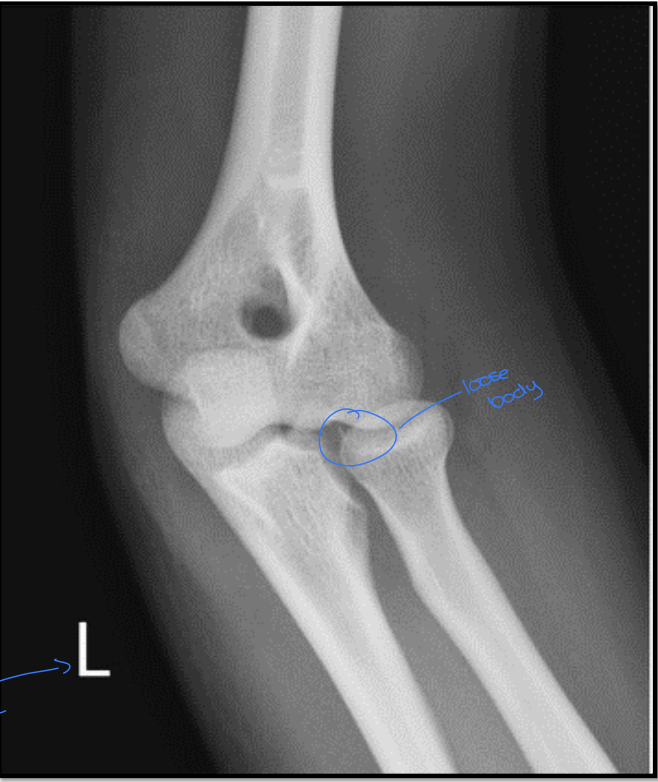

19

What is the positioning fault?

How would you fix it?

A

• hand is too low

• lateral condyle more distal

• need to raise hand